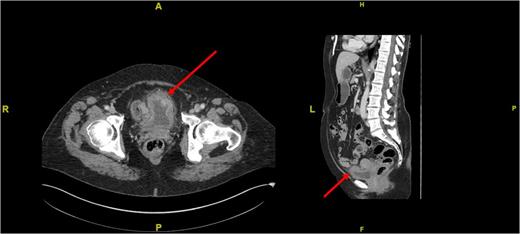

An urgent transurethral resection of the bladder tumour (TURBT) was performed which demonstrated a solid 4 cm tumour in the anterior wall of the urinary bladder. Resection was complete and tissue sent for histopathological analysis. A staging computed tomography (CT) scan post-op confirmed the absence of any locally advanced disease, lymphadenopathy or distant metastases (Fig. 2). Initial histopathological analysis reported the presence of muscle-invasive Grade 3 transitional cell carcinoma of the bladder with sarcomatoid change (G3pT2), but a supplementary report soon after confirmed positive smooth muscle actin (diffuse and tram track), anaplastic lymphoma kinase-1 (ALK1), focally positive CK7, AE1/3, weakly positive focally S100, and negative CD34, desmin, EMA, caldesmon, MNF116, p63. The sample was described as a highly cellular but monotonous appearing spindle-cell proliferation within the bladder, set in lightly myxoid stroma with scattered inflammatory cells. Overall, the features were in keeping with an IMT. Fluorescence in situ hybridization for ALK1 fusion was undertaken and studies of 103 cells, using the Cytocell ALK, chromosome 2p23-specific, dual colour probe showed that ALK rearrangement was present, confirming a diagnosis of IMT.

Cross-sectional (left) and sagittal (right) CT images of the abdomen and pelvis demonstrating a thickening of the anterior bladder wall at the site of the first TURBT (see red arrows).